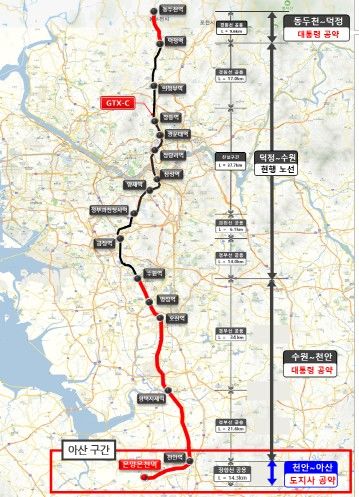

![[서울=뉴시스] 흉부X선에서 파운데이션 모델이 골다공증 판독을 위해 주목한 영역을 시각화한 이미지. (사진= 서울대병원 제공)](https://img1.newsis.com/2025/11/28/NISI20251128_0002005081_web.jpg?rnd=20251128094537)

[서울=뉴시스] 흉부X선에서 파운데이션 모델이 골다공증 판독을 위해 주목한 영역을 시각화한 이미지. (사진= 서울대병원 제공)

AI는 입력된 흉부 X선에서 척추와 늑골 같은 뼈 구조를 중심으로 특징을 추출하고, 이를 기존에 학습된 패턴과 비교해 정상(T-score ≥ -1.0), 골감소증(-2.5 < T-score < -1.0), 골다공증(T-score ≤ -2.5) 중 어떤 상태와 가장 유사한지를 판단한다.

연구팀은 여기에 더해 AI가 실제로 어떤 뼈를 근거로 삼아 판단하는지까지 확인할 수 있도록 '설명 가능성' 평가 체계를 설계했다. 뼈를 모두 가린 상태에서 특정 뼈 부위를 추가해 성능이 얼마나 향상하는지 확인하는 '차단 분석 방식'과 AI의 주목 영역이 실제 뼈 위치와 얼마나 일치하는지를 계산하는 '유의성 지도 방식'(IoUbone)을 통해, AI가 임상적으로 중요한 뼈 구조를 근거로 판단하는지를 정량적으로 검증했다.